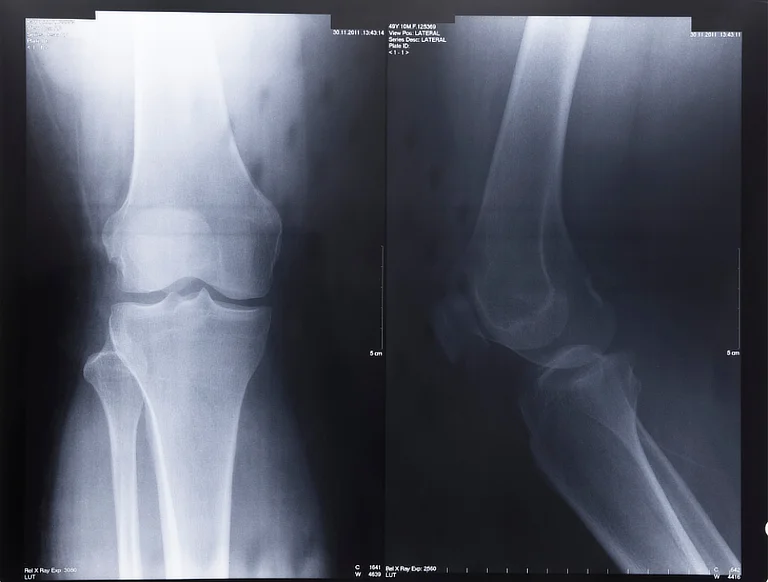

X-ray of osteoarthritic knee showing cartilage loss and bone spurs.

3. Imaging Tests – X-rays detect cartilage loss, bone spurs, and joint space narrowing, while MRI scans provide detailed images of soft tissues, helping to identify early cartilage damage and inflammation.

Diagnosing knee osteoarthritis involves a combination of physical examinations and imaging tests. Special tests include X-rays to detect cartilage loss, bone spurs, and joint space narrowing, while MRI scans may be used to evaluate soft tissue damage. In some cases, joint fluid analysis (arthrocentesis) is performed to rule out other conditions like gout or infection. It is best to consult a doctor or orthopaedic specialist for a thorough assessment of your condition.